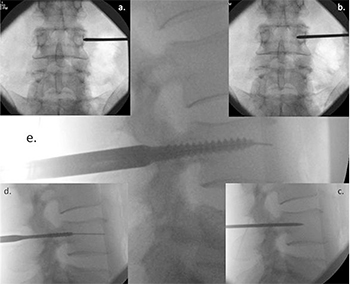

Fig. 2. Image intensifier radiographs of the percutaneous screw insertion technique showing: (a) anterior/posterior (AP) view of the Jamshidi needle docked onto the lateral

aspect of the pedicle – the ‘‘3 o’clock position’’; (b) AP view of advancement of the needle 20 mm to 25 mm into the vertebral body; (c) lateral view, checking the position of

the Jamshidi needle; (d) lateral view, the K-wire and tapping of the pedicle; and (e) lateral view, insertion of the pedicle screw.